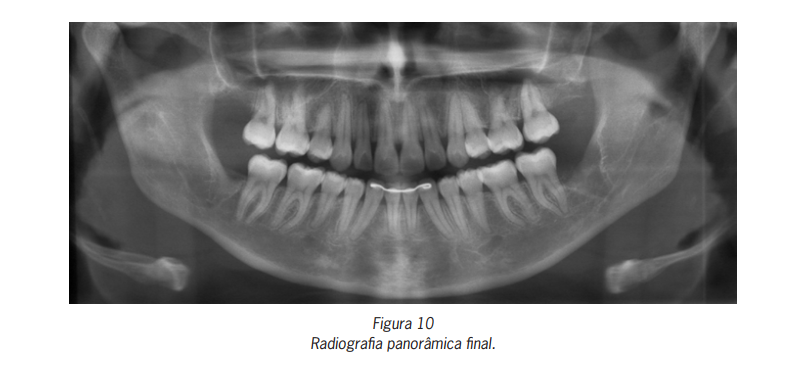

tratamento realizado (Figuras 9). Na radiografia panorâmica final, observa-se o posicionamento final dos incisivos inferiores

(Figura 10).